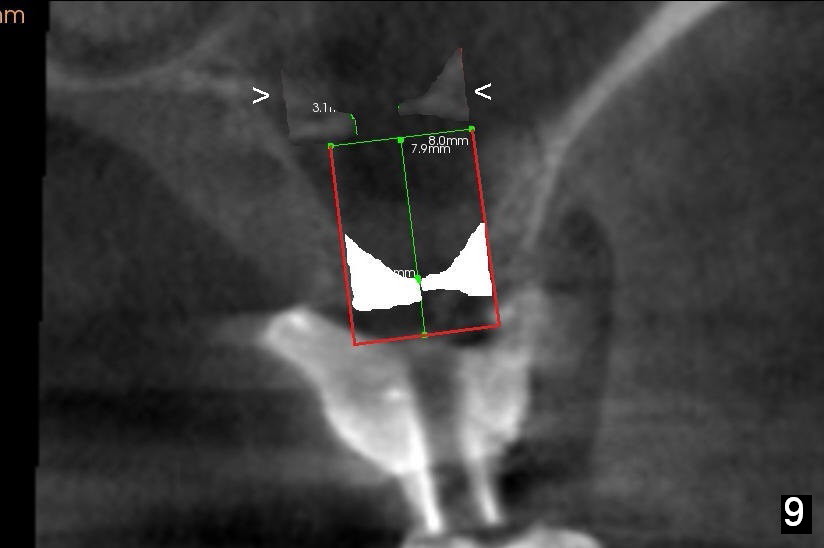

After crestal incision, a 3.5 or 4 mm trephine bur is used for 2 mm at #14. The regional sinus floor is lifted using a Bicon flat-end osteotome, followed by bone graft and taps. If the 6x11 mm tapered tap does not gain stability (Fig.3), use either 6x11 mm round tap (Fig.4) or 7 or 8x11 mm tapered tap (Fig.5). If the last does not work, try a larger round tap (Fig.6). In all, the sinus floor is pushed upstairs and an implant is inserted to be engaged into the sides of the sinus floor (Fig.7).

Coronally, a round implant does not appear to obtain more bone contact than a tapered one of the same diameter (Fig.8,10). Internal sinus lift works for this case?